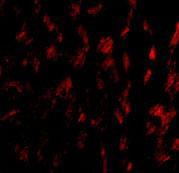

Immunofluorescence of GPVI in Human Heart tissue with GPVI antibody at 20 μg/mL. |